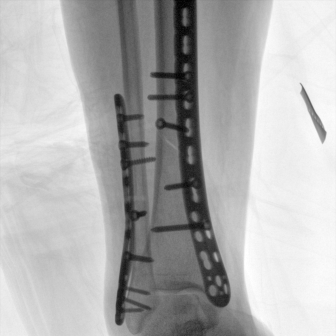

配備了兩種平板尺寸,大尺寸動態(tài)平板探測器成像面積較傳統(tǒng)平板探測器提升了25%以上,在視野需求大的手術中,便于醫(yī)生更好定位病灶點,規(guī)劃手術方案,減少因視野范圍不足而多次透視、點片造成的不便,不僅提高了手術效率,也減少了輻射劑量。

Clinical picture

臨床圖片